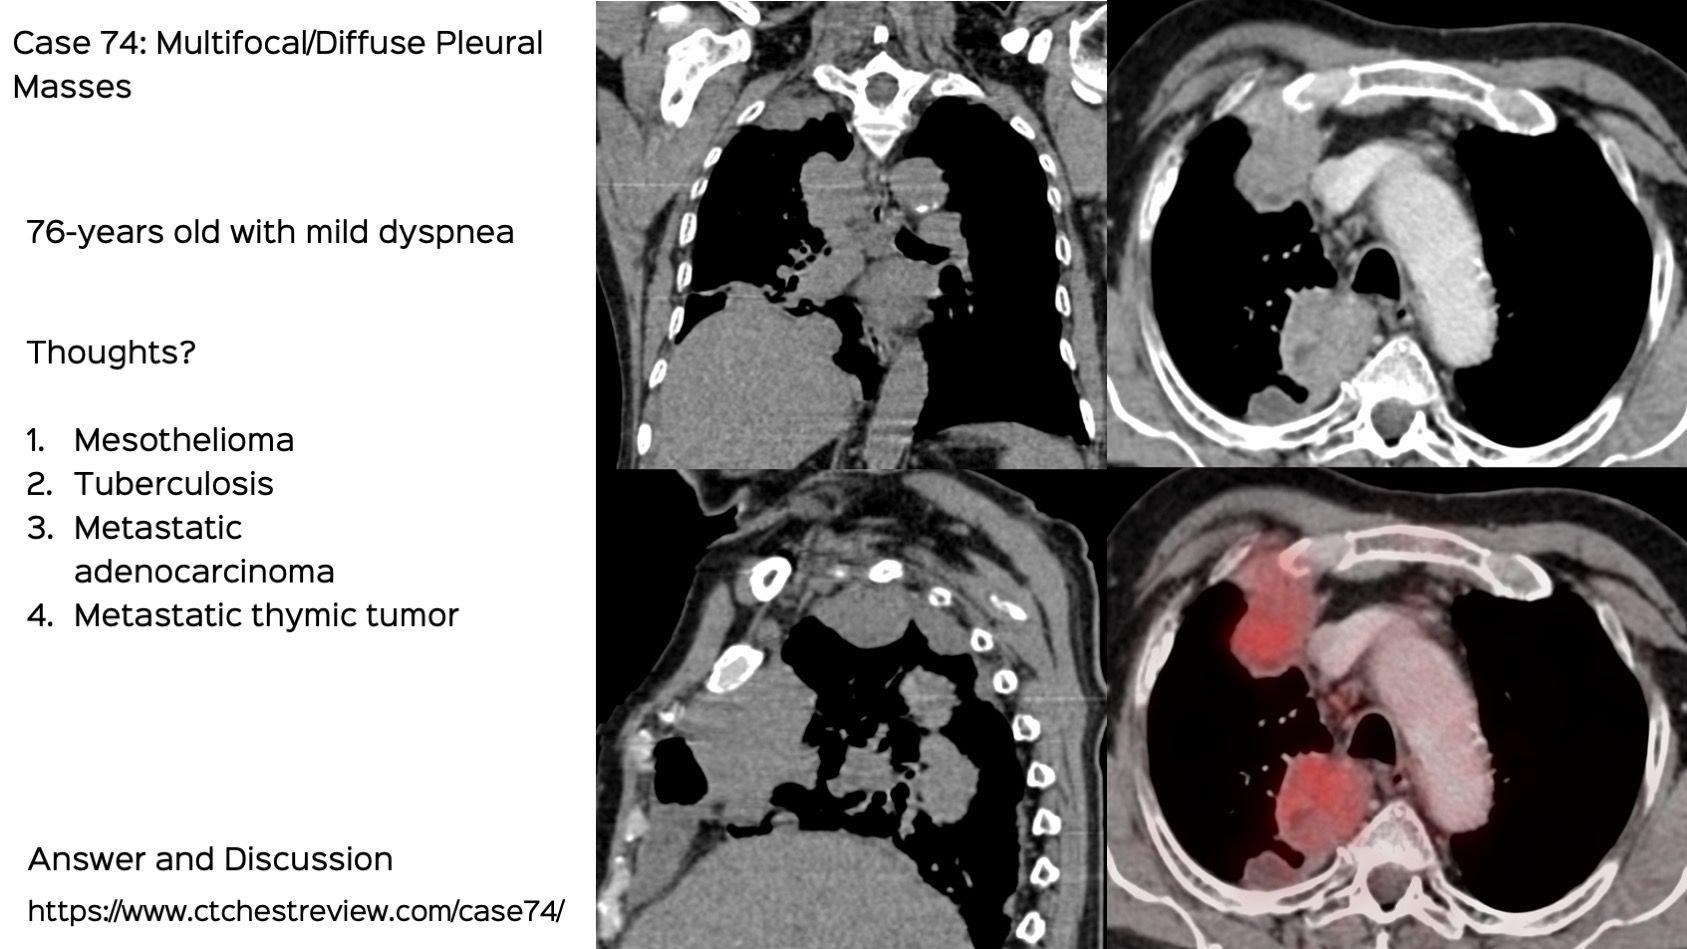

From www.ctchestreview.com

Case 74 Multifocal / Diffuse Pleural Disease Differential For Multifocal Pneumonia 37 the differential diagnosis includes alveolar proteinosis, infection (eg, pneumocystis jirovecii. Once again, there is a broad differential diagnosis for such findings. Consider this in three situations: (2) high risk for c. Involvement of a single lobe of the lung. (1) animal exposure (covers zoonotic pneumonias). Difficile infection (doxy reduces risk). Differential For Multifocal Pneumonia.